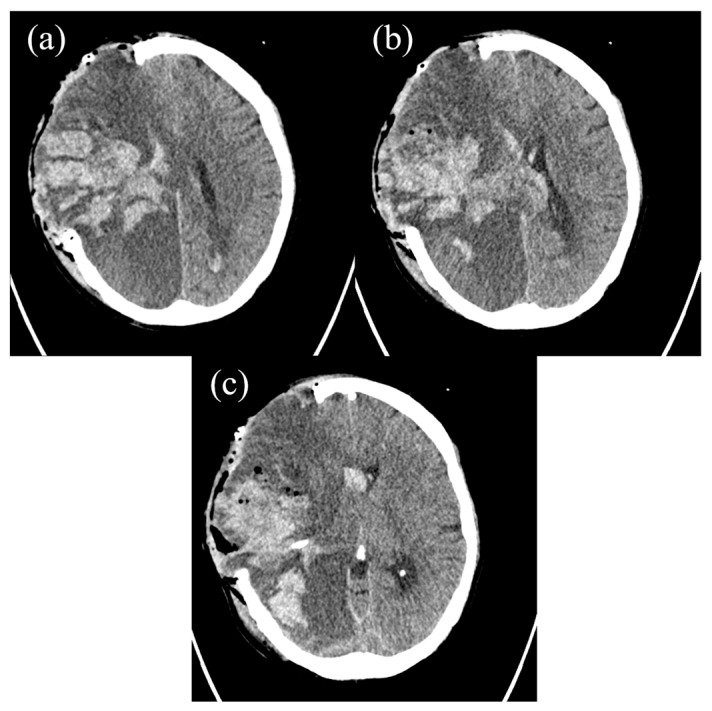

背景和临床意义:急性白血病是由未成熟前体细胞(“母细胞”)广泛增殖引起的造血系统肿瘤,主要发生在骨髓中。它们通常表现为模糊和非特异性的临床症状,使早期诊断特别具有挑战性。病例介绍:本病例报告描述了一位女性患者的临床过程,她最初因持续的牙痛而寻求牙科护理,这是一种非典型和误导性的症状。随后的检查显示诊断为急性白血病。虽然恶性肿瘤被及时发现并采取了适当的治疗措施,但疾病的发展速度惊人。患者最终出现了大量脑出血,这是一种可能与白血病相关凝血功能障碍有关的毁灭性并发症。尽管紧急的神经外科手术介入,出血证明是致命的。结论:该病例强调了在出现异常症状时提高临床怀疑的必要性,并说明了血液恶性肿瘤和凝血并发症之间复杂的相互作用。

Background and Clinical significance: Acute leukemias are neoplasms of the hematopoietic system that are caused by the extensive proliferation of immature precursor cells ('blasts'), mainly in the bone marrow. They frequently manifest with vague and non-specific clinical symptoms, making early diagnosis particularly challenging. Case Presentation: This case report describes the clinical course of a female patient who initially sought dental care due to a persistent toothache-an atypical and misleading symptom. Subsequent investigations revealed a diagnosis of acute leukemia. Although the malignancy was identified promptly and the appropriate therapeutic measures were initiated, the disease progressed with alarming rapidity. The patient ultimately developed a massive intracerebral hemorrhage-a devastating complication likely related to leukemia-associated coagulopathy. Despite emergent neurosurgical intervention, the hemorrhage proved fatal. Conclusions: This case highlights the critical need for heightened clinical suspicion in the presence of unusual symptoms and illustrates the complex interplay between hematologic malignancies and coagulopathic complications.